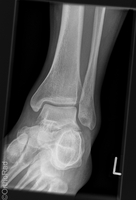

Sprunggelenk

Snowboard fracture Talus